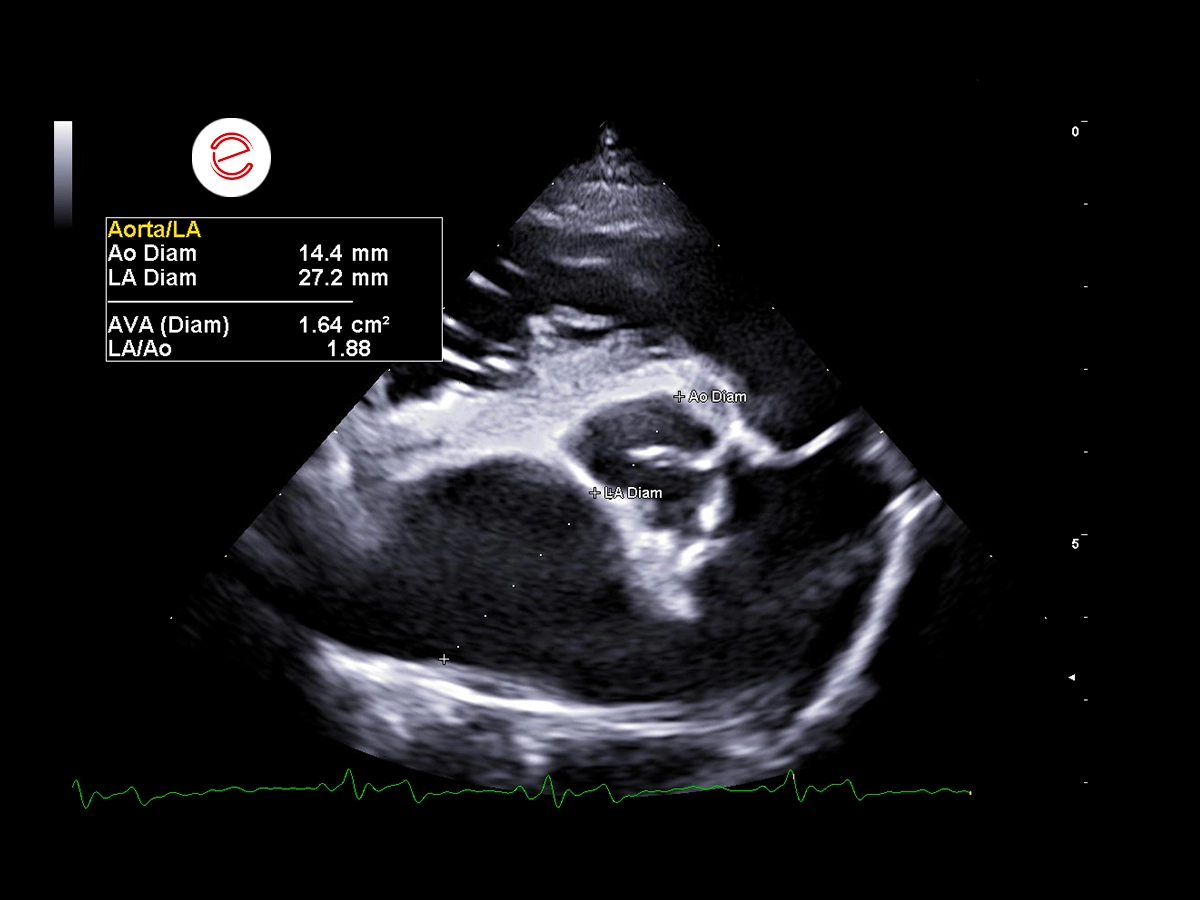

Echocardiographic measurements demonstrated left atrial enlargement, supported by an elevated LA/Ao ratio of 1.88, which is above the normal limit (<1.6). This is consistent with chronic volume overload and the potential progression of underlying cardiac disease.